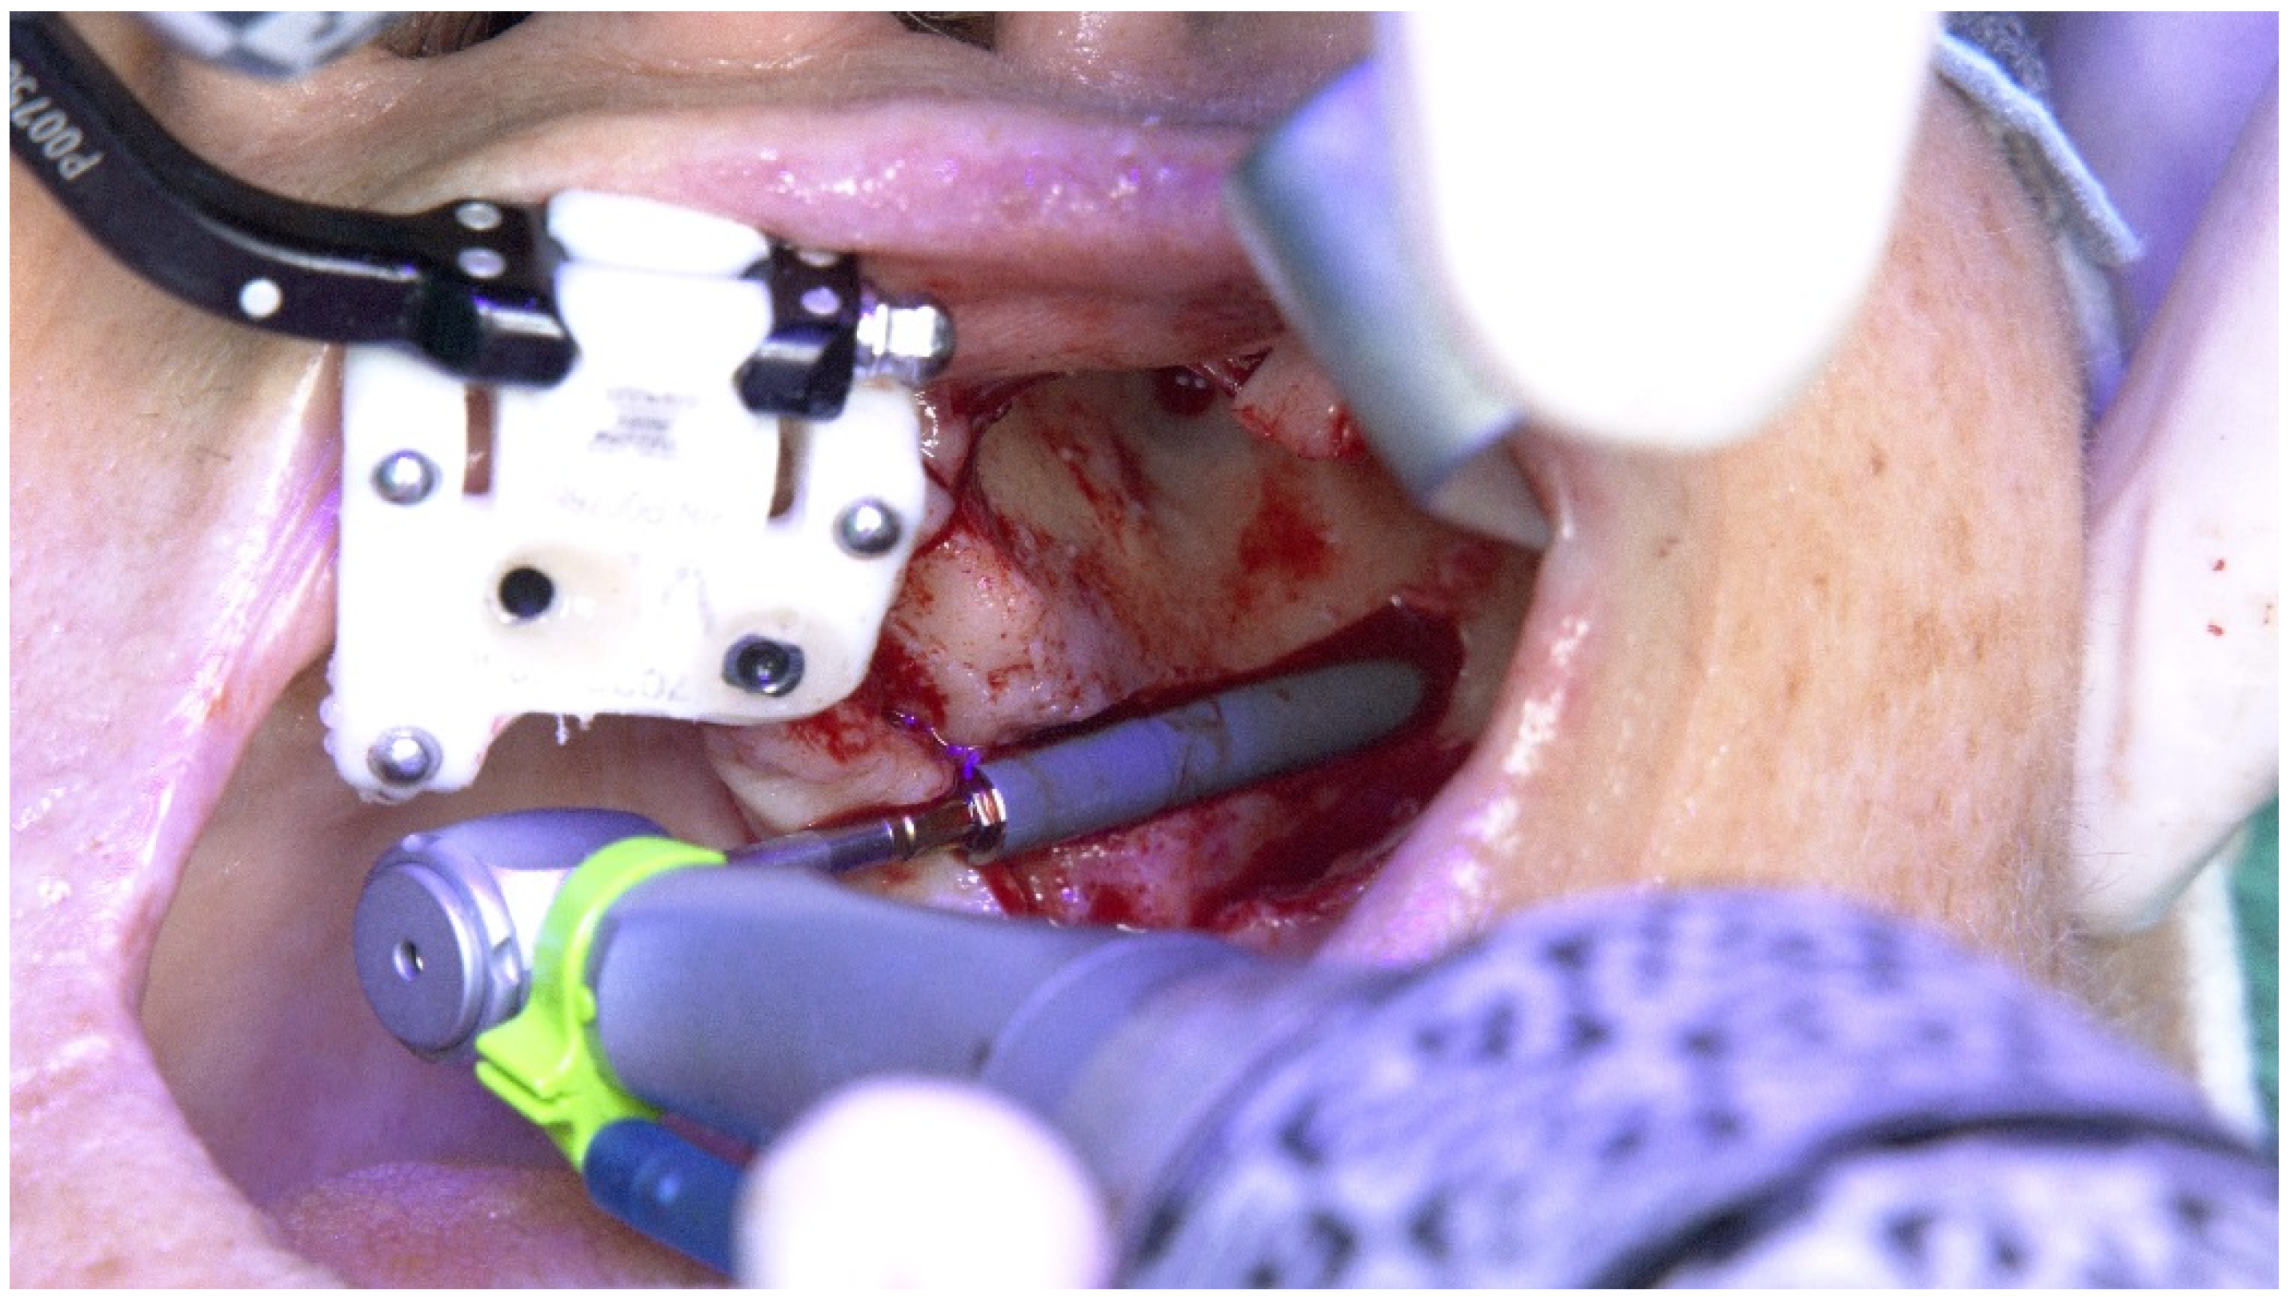

2.1. Patient 1

2.2. Patient 2